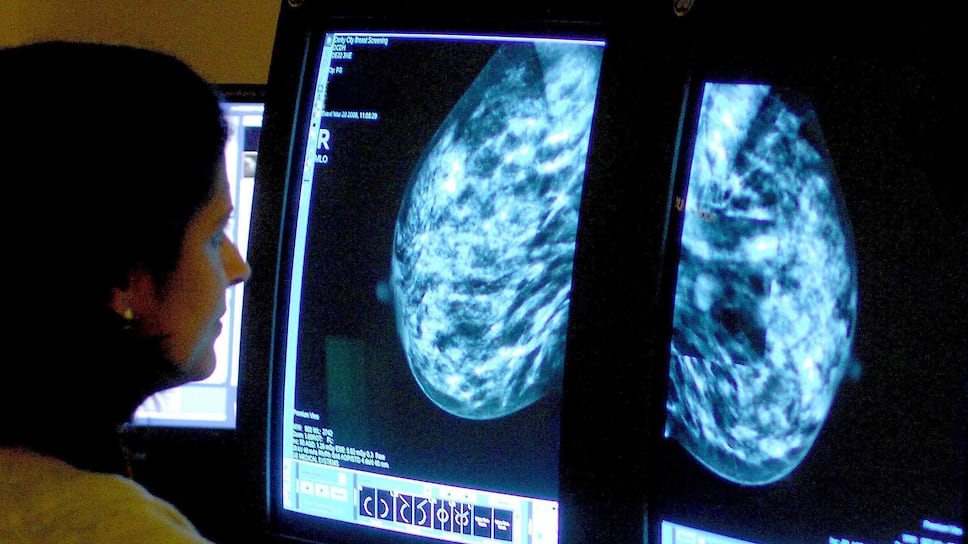

Фото: PA Images \ TASS

В Москве 12 октября состоялся второй Евразийский форум по раку молочной железы, собравший онкологов из США, Швейцарии, Франции, Румынии, Индии, Великобритании и России. Онкологических заболеваний в мире насчитывается несколько тысяч разновидностей, а главное, что стремятся сделать ученые,— выявлять их максимально на ранних стадиях.